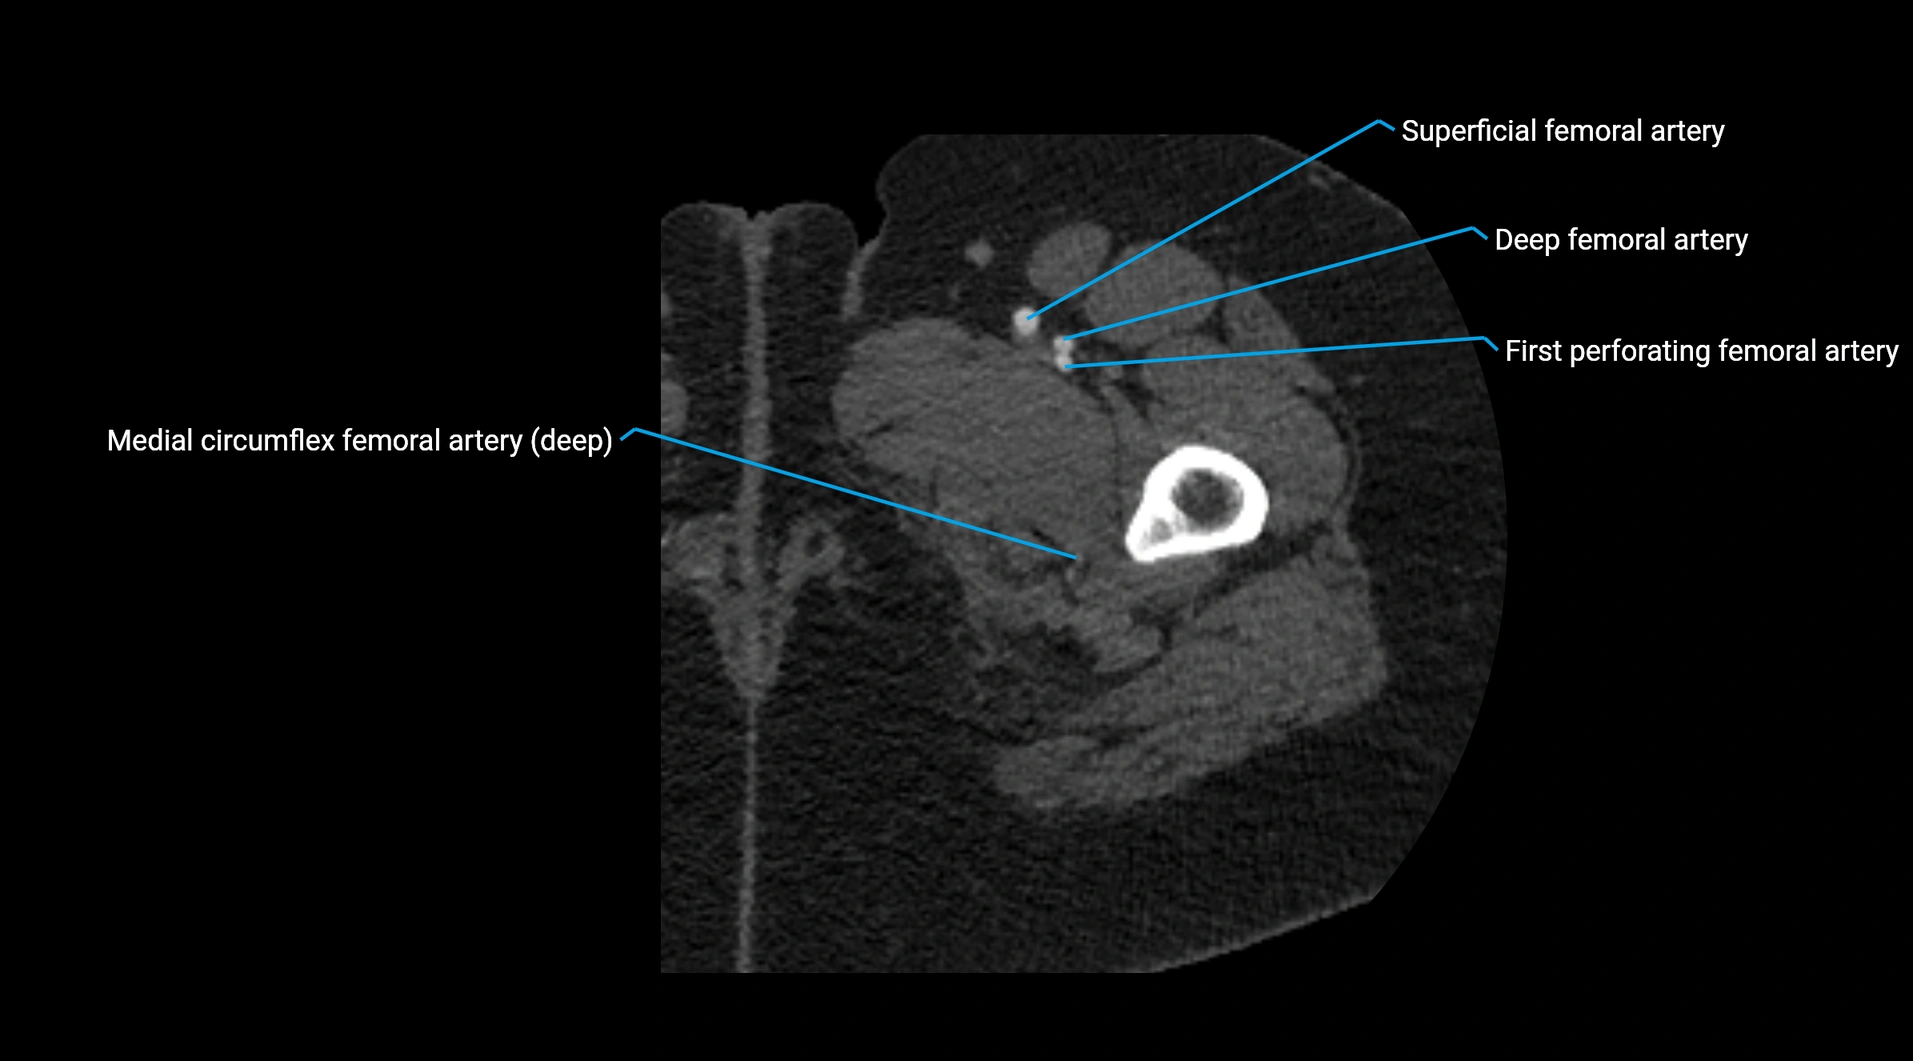

Contrast-enhanced CT (CTA):

• Gold standard for abdominal aortic imaging

• Provides excellent detail of lumen, wall, aneurysm, thrombus, and branch vessels

• Multiplanar and 3D reconstructions help in aneurysm measurement, stent graft planning, and dissection evaluation

• Detects acute rupture, traumatic injury, or occlusion with high sensitivity